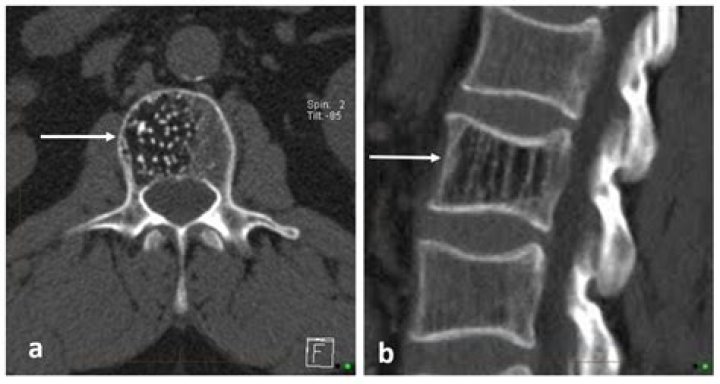

Vertebral hemangiomas or haemangiomas are a common vascular lesion found within the vertebral body of the thoracic and lumbar spine. These are predominantly benign lesions that are often found incidentally during radiology studies for other indications and can involve one or multiple vertebrae.

Aggressive vertebral hemangiomata are a rare form of vertebral hemangiomata where significant vertebral expansion, extra-osseous component with epidural extension, disturbance of blood flow, and occasionally compression fractures can be present causing spinal cord and/or nerve root compression 1,2.